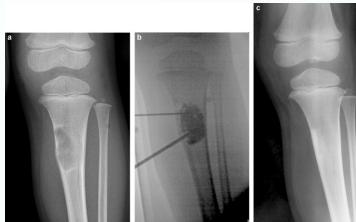

Simple Bone Cyst

- Solitary – unicameral

- Children

- Metaphysis:

- Prox. Humerus and Femur

- Not a tumor:

- Not seen in adults

- Heals spontaneously

- Pathological fracture / or incidental

- Aspirate is clear straw-colored

Treatment

- Small, reducing in size:

- Leave alone

- Increasing in size, active:

- Moderate trial of bone marrow injection

- Large (risk of fracture) Curettage & grafting

- Pathological fracture:

- Treat fracture

- Cyst might heal

- Recurrent / injection failed:

- Surgical curettage and bone grafting